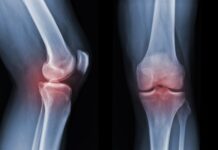

In caso di gonartrosi, una soluzione può arrivare dal plasma arricchito di piastrine (PRP, Platelet-Rich Plasma) in grado di fermare la degenerazione cartilaginea. Artrosi di anca e ginocchio sono tra le patologie degenerative dell’apparato muscoloscheletrico più diffuse al mondo. La loro forte correlazione con l’invecchiamento ne fa, inoltre, due condizioni in costante crescita all’interno della popolazione mondiale.

Un recente studio giapponese, condotto su un modello animale, mostra la capacità del plasma arricchito di piastrine di sopprimere il deterioramento delle cartilagini del ginocchio in un topo con gonartrosi. Pubblicato su Regenerative Therapy, lo studio è stato condotto presso la Juntendo University di Tokyo.